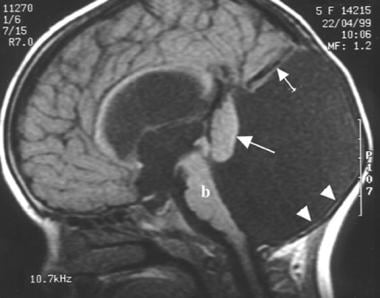

Dandy Walker Syndrome, Penyakit Sporadis yang Mengambil Adam Fabumi

Penyakit dandy walker syndrome merenggut nyawa bayi Adam Fabumi pada Rabu, 22 November 2017. Ternyata, penyakit ini telah diderita Adam semenjak masih berada dalam kandungan ibunya, Ratih Megasari. Orangtuanya selalu mengunggah setiap perjuangan bayi Adam melawan penyakit ini ke akun instagram @adamfabumi yang dikelola keduanya.

Dandy walker syndrome termasuk langka dan sporadis, karena terjadi hanya setiap 30 ribu kelahiran hidup. Diagnosis prenatal dan prognosisnya bisa jadi sulit, namun masih terdapat kemungkinan bahwa diagnosis prenatal bisa dilakukan melalui ultrasound.